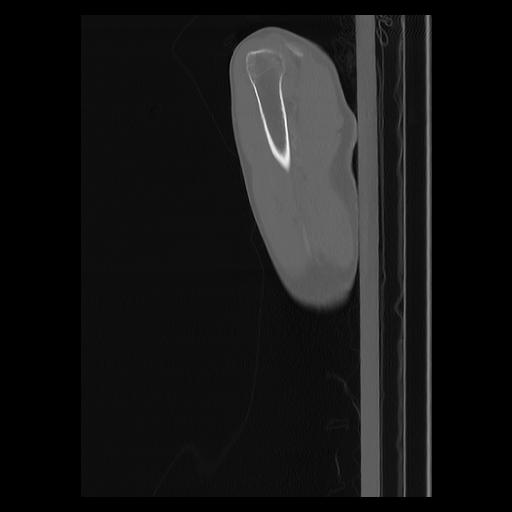

33 PULMON,CE,Sagittal,3.000,PULMON,Sagittal,